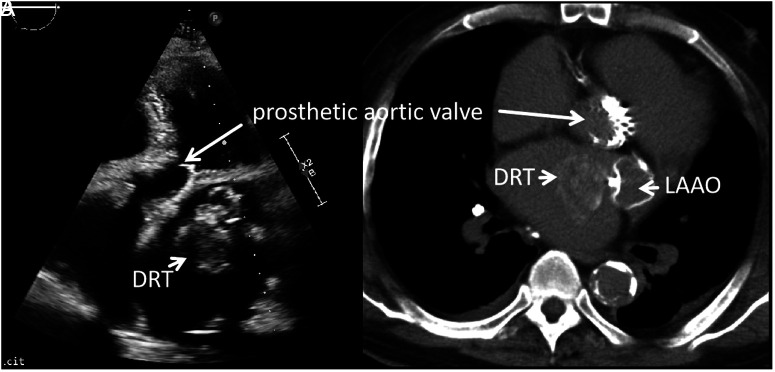

A Rare Case of a Decade-Long Device-Related Thrombus with a Unique "Tree-Ring" Structure.